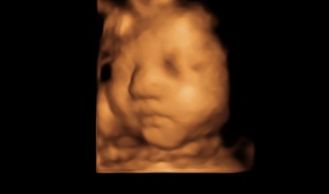

四维录像适于package1和package2,录像的最佳时间为22-28周

周数越大,局部越清晰,适于18-34周

四维除了看胎儿颜面部外,还可以看手脚及胎儿心跳活动

1第二阶段扫描,此期间皮下脂肪较为饱满,局部器官更为清晰,面部表情丰富,如吃手指,喝羊水,打哈欠

怀孕34周可以选择package3照片组,脸部饱满,脸部轮廓非常清晰